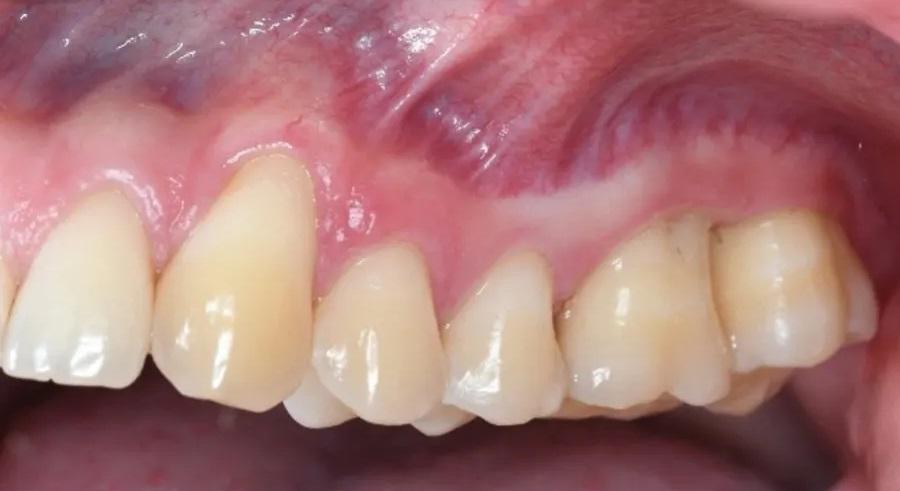

Фото 1 и Фото 2. Внеоральный осмотр выявил легкую болезненность в левом ВНЧС; интраоральный осмотр показал тонкий фенотип десны, локализованную рецессию десны и потерю клинического прикрепления. Предоперационные вестибулярный (Фото 1) и окклюзионный (Фото 2) виды показали воспаление десны, минимальную рецессию и глубину зондирования 12 мм с вестибулярной поверхности зуба № 2.6.